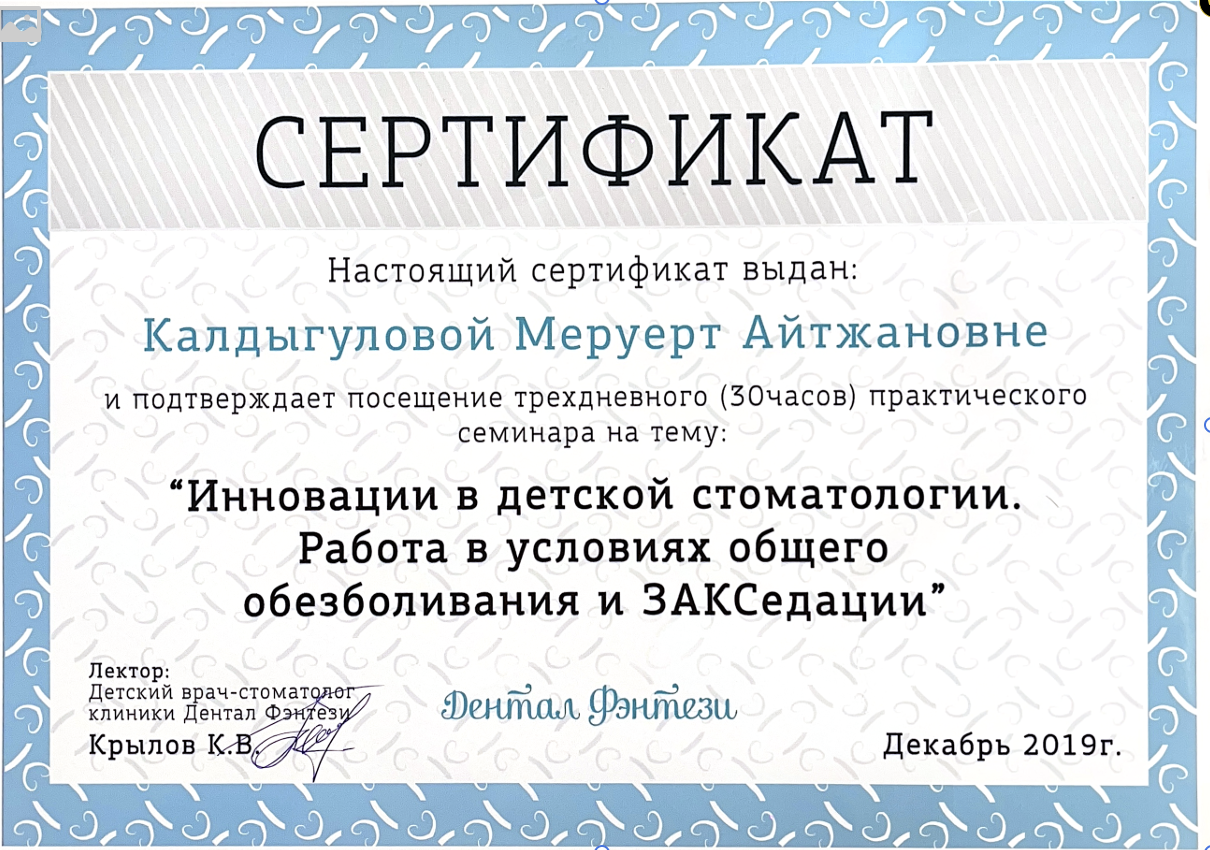

Калдыгулова Меруерт Айтжановна

Регулярно совершенствует знания в стоматологии